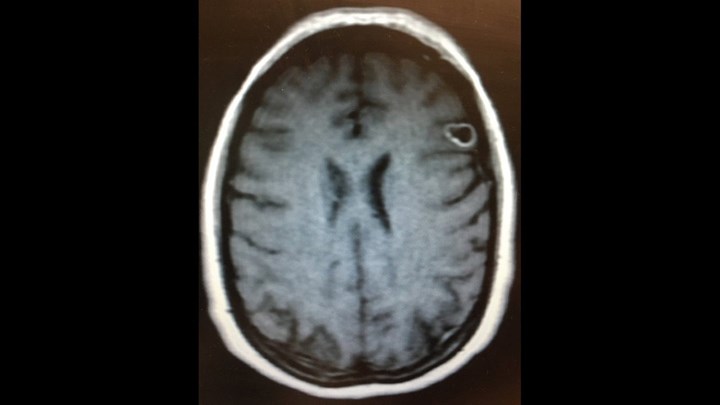

Οι συνάδελφοι του Ζου τον έστειλαν γρήγορα στο νοσοκομείο στη διάρκεια ενός τέτοιου επεισοδίου όπου η αξονική τομογραφία έδειξε ότι ο άνδρας είχε “ενδοκρανιακά ασβεστώματα” και άλλες βλάβες στον εγκέφαλό του. Αρνήθηκε περαιτέρω εξετάσεις για να μην πληρώσει περισσότερα χρήματα και επέστρεψε σπίτι του. Ωστόσο, τα συμπτώματα δεν υποχωρούσαν και οι κρίσεις συνεχίζονταν. Τελικά πήγε στο Πανεπιστημιακό Νοσοκομείο όπου έπειτα από μαγνητική τομογραφία διεγνώσθη με σκουλήκια στον εγκέφαλο.